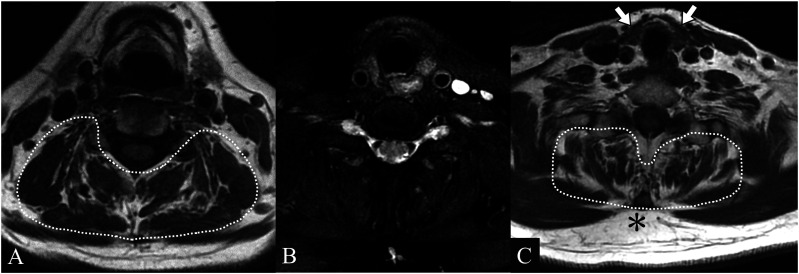

Dropped head syndrome, characterized by excessive flexion of the neck, frequently leads to significant impairment in quality of life. Among the various causes of this syndrome, some cases respond effectively to internal medicine. We report a case of a woman in her 70s who presented with dropped head syndrome and was finally diagnosed with hypothyroid myopathy limited to the extensor muscles of the neck. Cervical spine MRI at the initial examination indicated thyroid atrophy, increased subcutaneous fat, and a mild high signal in the right cervical extensor muscles on fat-suppressed T2-weighted images. Blood tests confirmed hypothyroidism. Treatment with levothyroxine improved the symptoms and normalized the blood test results. This case highlights the importance of careful evaluation of the thyroid gland and paravertebral muscles in cervical spine MRI. They can offer diagnostic clues for underlying the important causative role of thyroid disease in dropped head syndrome.